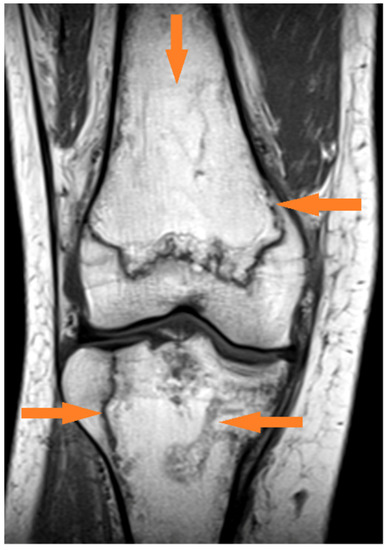

3.1.1. Case 1 (Patient No. 5)

| 5 | both knees | 21 | no | 2 | 8 | 7 | 1 |